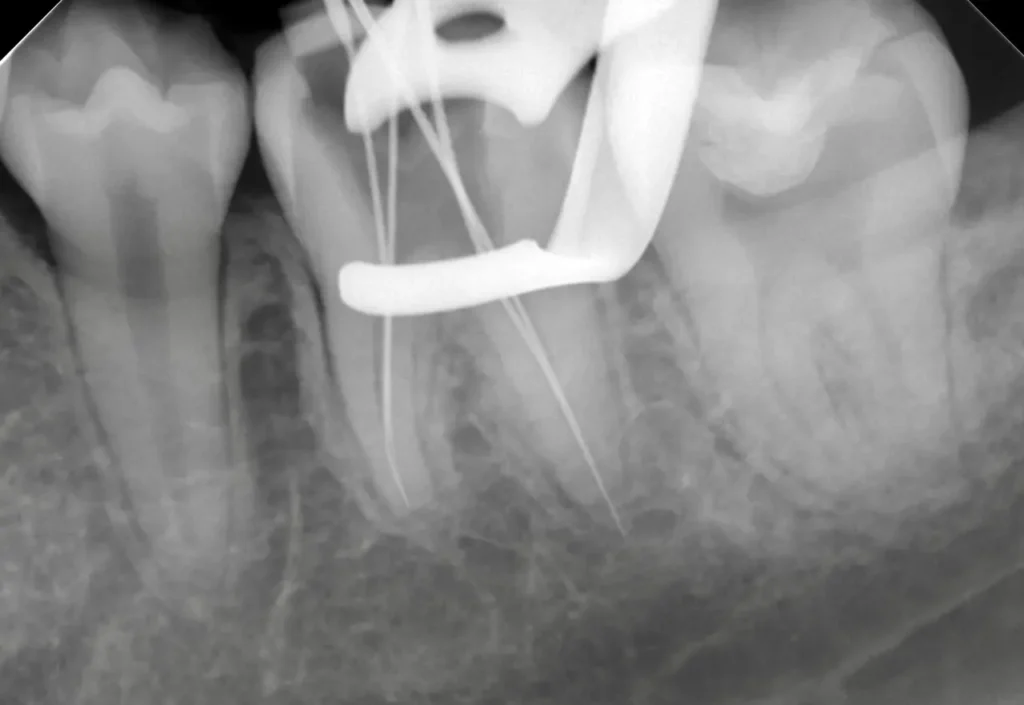

術中(ファイル試適)

レントゲン写真

ラバーダムシートを固定する金具が写っています、シートはバイ菌が

入らないように撮影時にも外しません